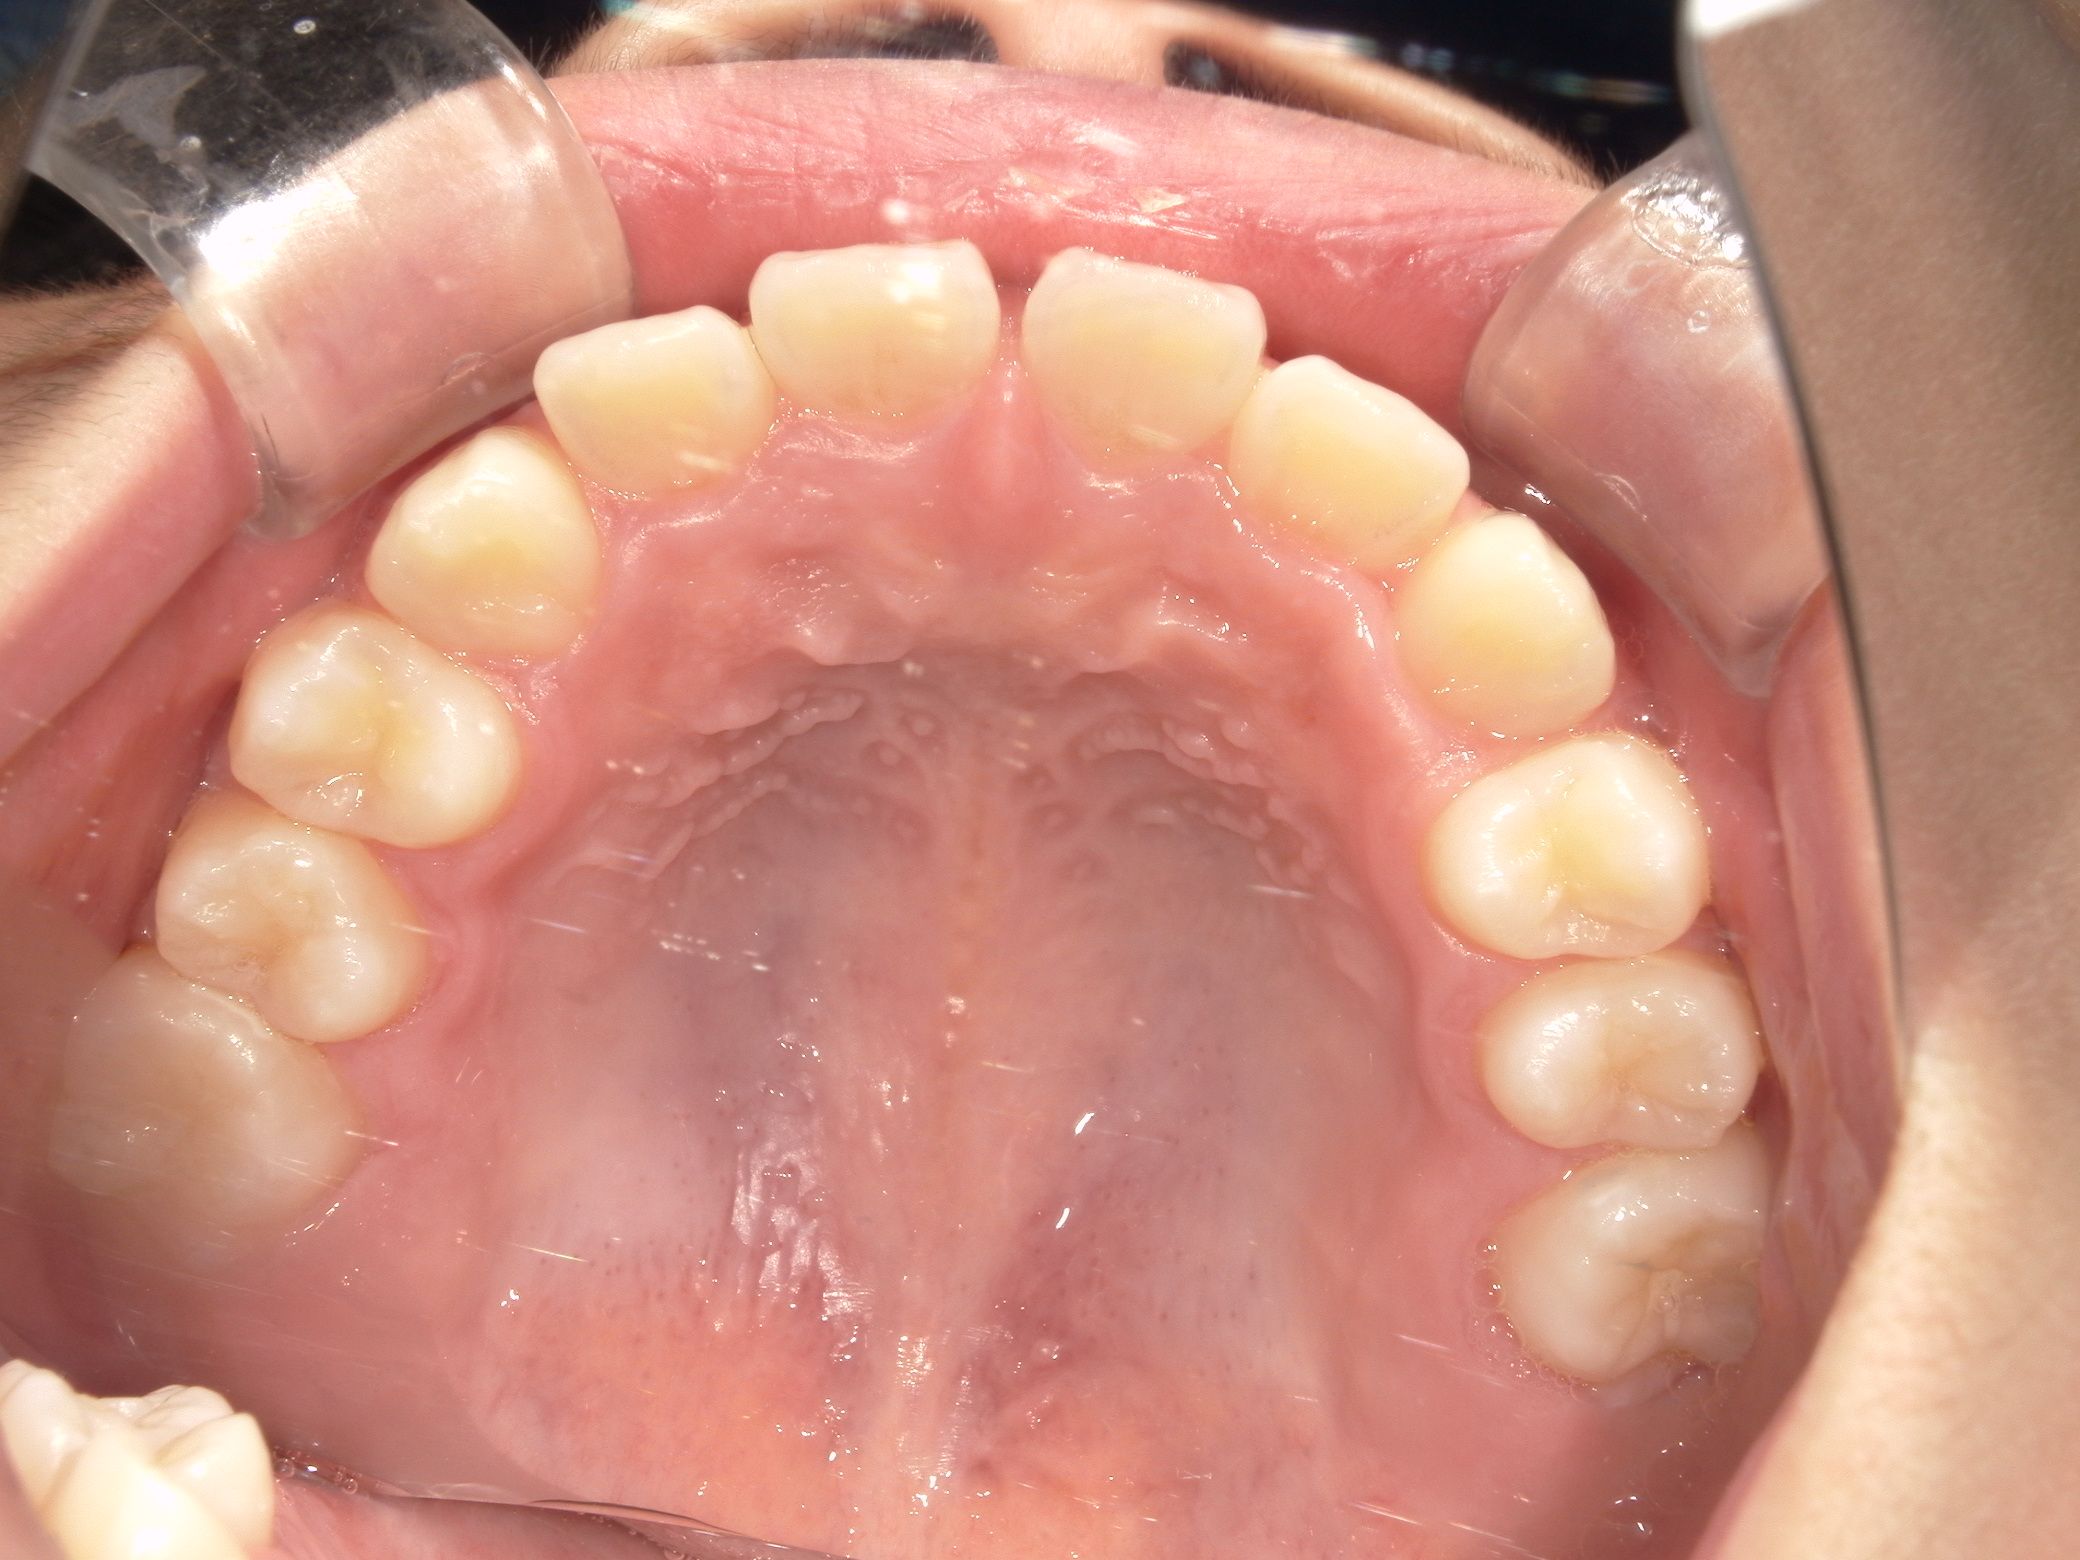

治療前 Before

上の歯並びがガタついています